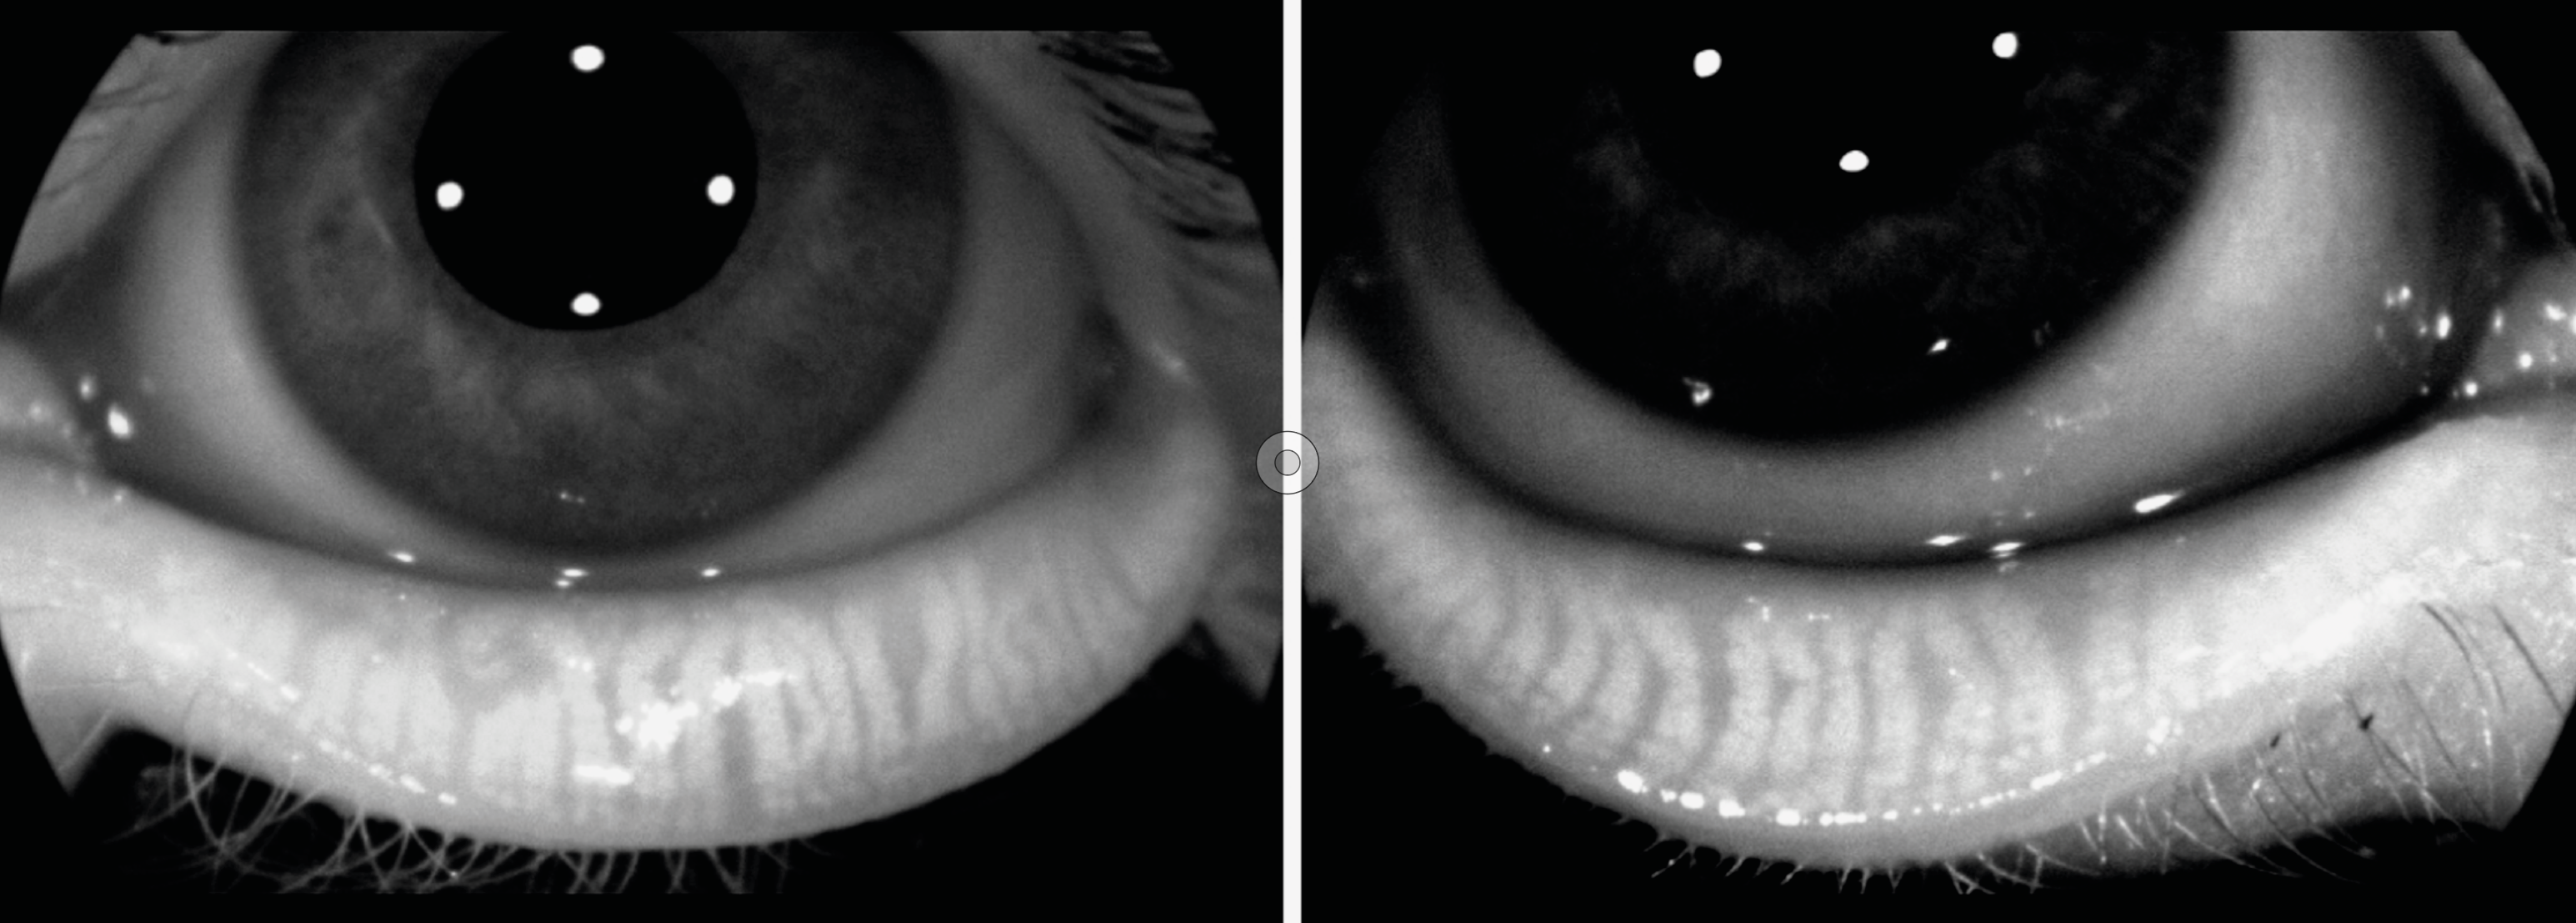

Figure 3. A. Taches de Bitôt OD/OG au moment du diagnostic en lumière blanche, puis en lumière bleue avec instillation de fluorescéine : notez l’aspect « vers luisants » de la conjonctive temporale.

B. Disparition des taches à 3 mois de la supplémentation vitaminique OD/OG.